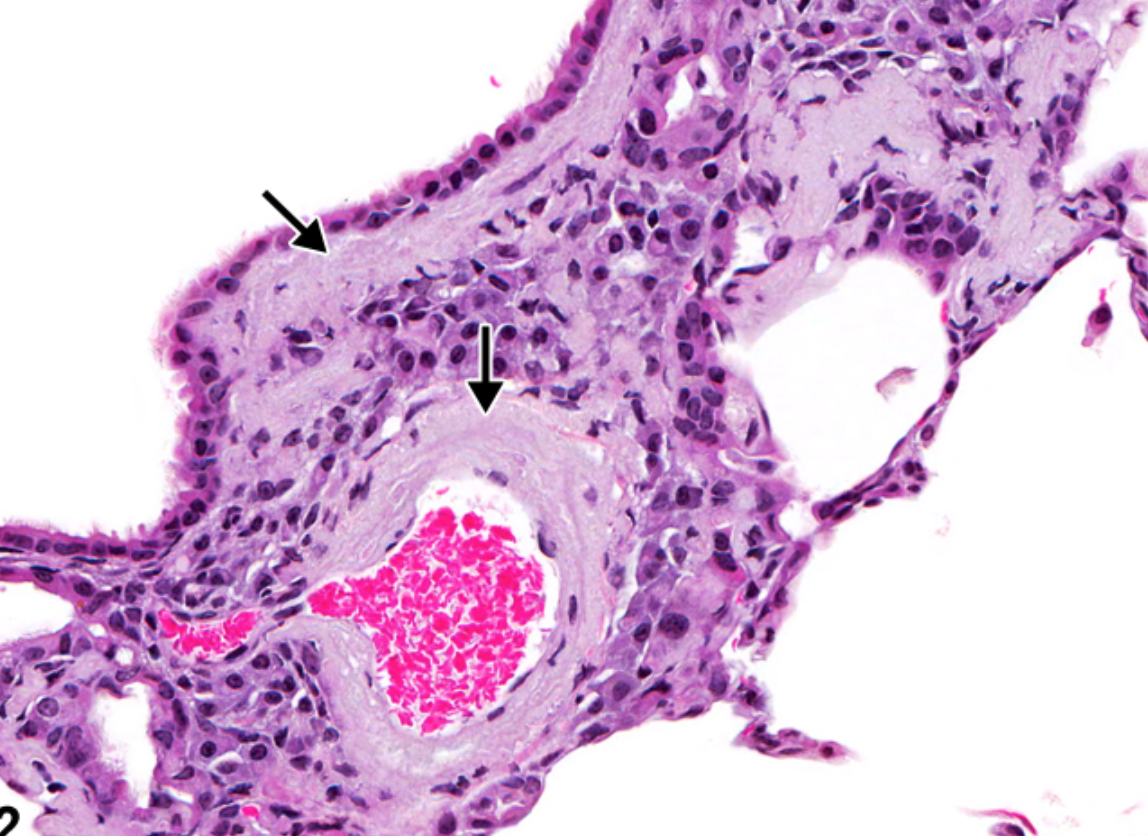

Bild: Lunga med amyloid.